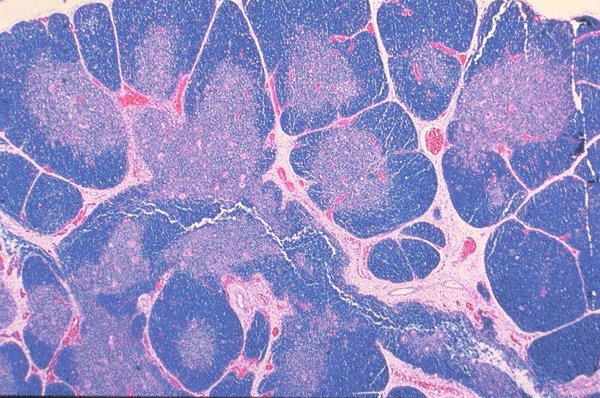

Set 4 Hematopathology of Lymph Nodes, Spleen, and Other Organs

Slide 10 of 212 Image ID 4617

Thymus (newborn)

This H&E stained view is of a thymus gland from a

newborn. The cortical and medulary areas can be

appreciated.